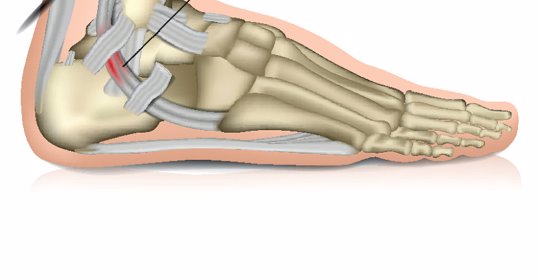

偏身萎縮:腓神經傷害的治療方法與垂足症的恢復